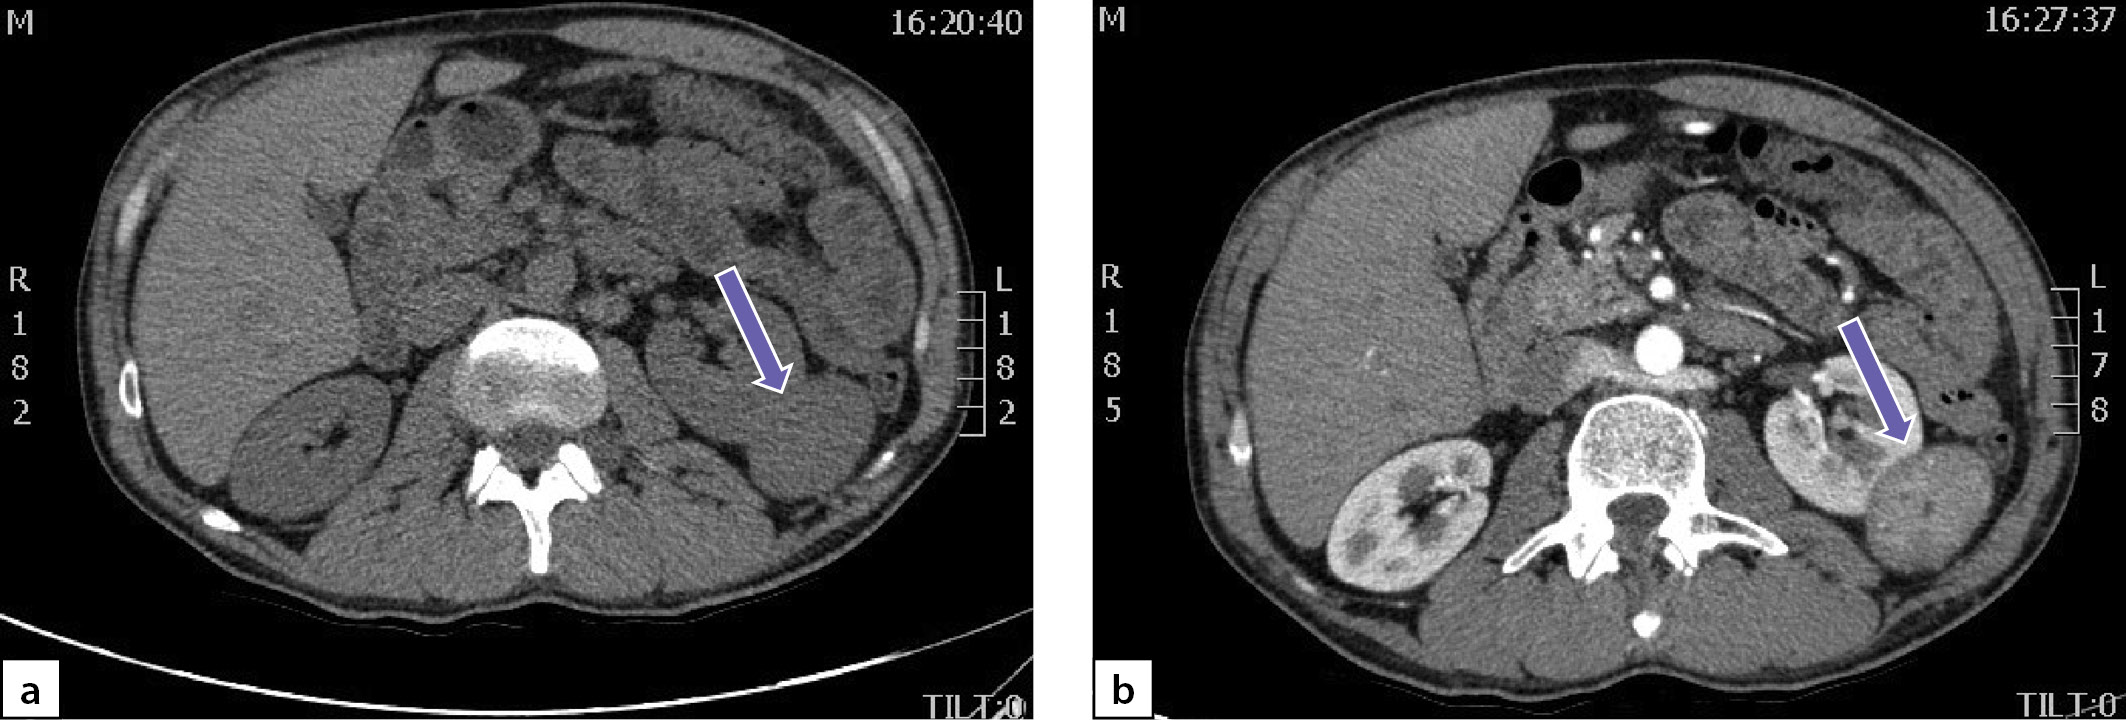

По данным мультиспиральной компьютерной томографии (МСКТ) брюшной полости и забрюшинного пространства с в/в контрастным усилением: в правом надпочечнике, занимая все его пространство, определяется объемное образование с четкими контурами, размерами 80х75х85 мм, плотностью в артериальную фазу 66 НU, в венозную фазу 69 НU, в паренхиматозную фазу 62 НU, в отсроченную до 51 НU (рис. 2 a, b). Кроме того, в забрюшинном пространстве, слева, с деформацией левой почки на уровне средней трети, определяется объемное образование размерами 49х37х47 мм, преимущественно мягкотканой плотности 31 НU, неоднородной структуры, с наличием участков пониженной плотности. Накопление контрастного вещества в артериальную фазу 86 НU, в венозную фазу 112 НU, в паренхиматозную фазу 85 НU, в отсроченную до 62 НU (рис. 3 a, b).

Рисунок 3. Образование забрюшинного пространства слева:

а) нативная фаза; b) после введения контрастного препарата.

Figure 3. Formation of the retroperitoneal space on the left:

a) native phase; b) after administration of a contrast agent

Учитывая молодой возраст пациента, злокачественный КТ-фенотип выявленных образований и наличие артериальной гипертензии, у пациента были все основания для исключения ФХЦ.

Через 6 месяцев после хирургического лечения отмечена нормализация АД без антигипертензивных препаратов. Уровни производных катехоламинов в суточной моче существенно снизились, однако полностью не нормализовались: метанефрины — 115 мкг/сут (2,9–52), норметанефрины — 208 мкг/сут (5,7–67). По данным МСКТ брюшной полости и забрюшинного пространства с в/в контрастным усилением, в забрюшинном пространстве слева визуализируется объемное образование размерами 52х38х49 мм (ранее 49х37х47мм), преимущественно мягкотканой плотности (31 НU), неоднородной структуры, с наличием участков пониженной плотности, которое деформирует левую почку на уровне средней трети; накопление контрастного препарата в артериальную фазу 86 НU, в венозную фазу 112 НU, в паренхиматозную фазу 85 НU, в отсроченную до 62 НU (рис. 6).

Рисунок 6. Образование забрюшинного пространства слева:

Figure 6. Formation of the retroperitoneal space on the left:

a) native phase; b) after administration of a contrast agent.